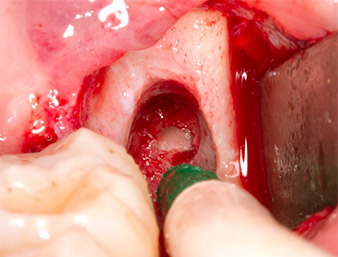

Piezomed B5

Imagen 5: Con un inserto piezoquirúrgico con forma de cincel (Piezomed B5) se eleva el hueso en el área de los alvéolos. Tras la retirada del resto radicular, este sirve como material de aumento autólogo (véase figuras 13 y 14).

El tejido autógeno se extrajo con la punta de trabajo en forma de pala del inserto y se guardó en solución salina fisiológica hasta su posterior utilización (véase figura 13).

Con el fin de preparar el resto radicular de forma libre sin dañar el tejido, se utilizó otro inserto (Piezomed S2), que está indicado sobre todo para la preparación de la ventana lateral en los aumentos de la base del seno maxilar. Además, se utilizó la esfera diamantada para alisar los bordes óseos afilados (figuras 6 y 7). Todos los accesorios Piezomed se utilizaron con el ajuste estándar automático correspondiente sin función de refuerzo de la potencia.

Piezomed S2

Imagen 6: Con un inserto esférico diamantado (Piezomed S2) el resto radicular se preparó de forma libre con cuidado y los bordes óseos se alisaron.